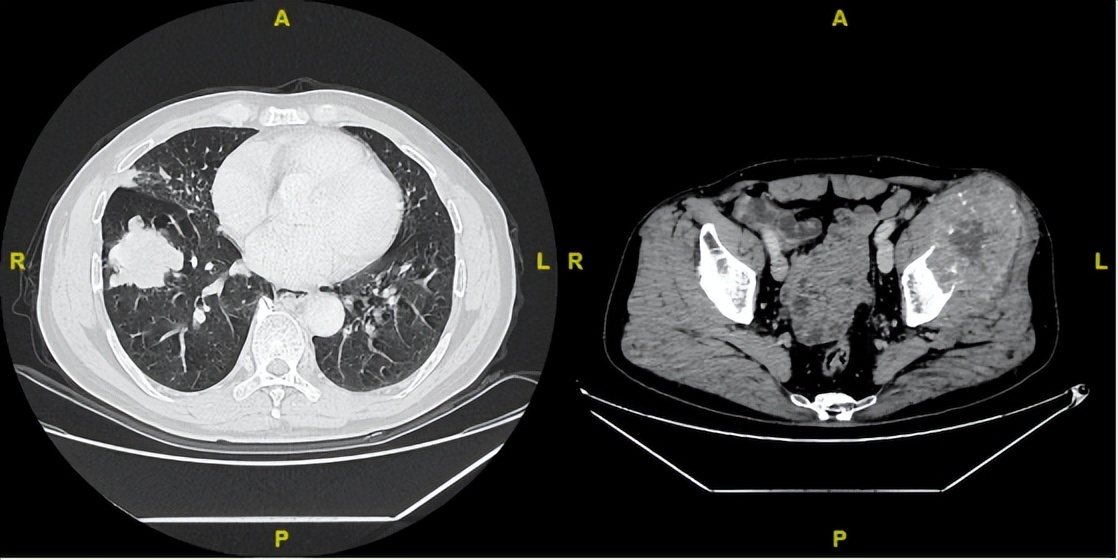

2024年2月19日

△治疗后不同随访时间的胸部及髋关节CT病灶变化